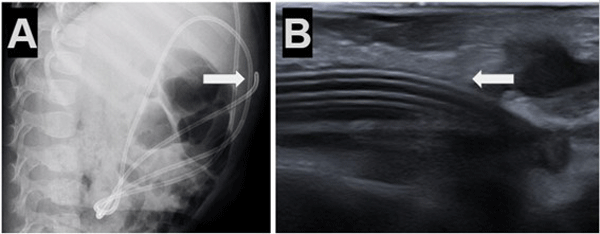

Caso 5. Paciente femenina de 1 año con antecedente de tumor de fosa posterior e hidrocefalia tratada con DVP al mes de vida, presentó episodios de vómitos y somnolencia con dilatación del sistema ventricular en comparación con estudios previos por tomografía simple de cerebro. Radiografías de sistema confirmaron migración subcutánea y retrógrada del catéter distal (Figura 5).

Figura 5. Caso 5: A) Se observa Rx de tórax y abdomen (perfil) con catéter distal a nivel abdominal con migración retrógrada. B) Ecografía abdominal: muestra ingreso y salida de catéter distal por mismo sitio; imagen típica de catéter en “doble caño” con signo ecográfico “caño de escopeta” (flecha blanca).

En nuestra experiencia, con los cinco casos presentados, luego de evaluar en forma detallada el cuadro clínico y las imágenes de cada paciente, planteamos una estrategia quirúrgica diferente a la revisión convencional del sistema de derivación ventriculoperitoneal: en lugar de reincidir y realizar la apertura de la cicatriz cefálica, optamos directamente por la apertura de la incisión abdominal previa y realizamos la exploración y revisión del catéter distal, en todos los casos evidenciamos la salida de líquido cefalorraquídeo a través de este, motivo por el cual asumimos los cuadros como disfunciones parciales del sistema por localización ectópica de la punta del catéter distal. Se reposicionó el catéter dentro de la cavidad peritoneal en todos los pacientes con cierre de la celiotomía y fijación del catéter mediante la técnica de sutura tipo “bolsa de tabaco”; con esta maniobra se logró el correcto funcionamiento del sistema con buena evolución postoperatoria y sin intercurrencias, preservando de esta forma la integridad de la cicatriz cefálica. En el último caso, además, nos apoyamos en la ecografía intraoperatoria para mejor localización del catéter, una herramienta de amplia disponibilidad que recomendamos utilizar, ya que de forma rápida y segura nos permite tener una imagen en tiempo real y a un bajo costo. Este enfoque quirúrgico reduce las posibilidades de complicaciones tales como infecciones asociadas a prótesis al reducir el tiempo quirúrgico y la exposición de la porción cefálica del sistema, acorta los tiempos de anestesia minimizando reacciones adversas y efectos secundarios a la misma, además favorece una recuperación postoperatoria más rápida, reduciendo la estancia hospitalaria optimizando recursos y disminuyendo los costos para el sistema de salud.